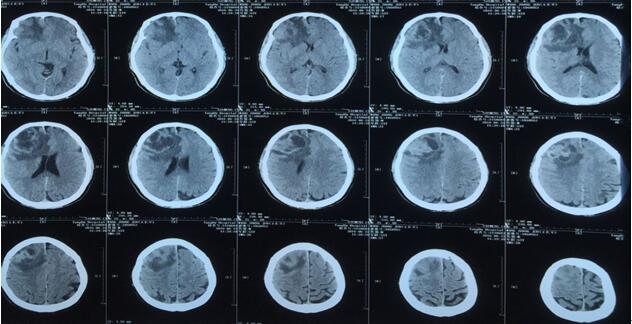

患者王某某,男,53歲,因“間斷頭痛半月”入神經內科十二病區,發現顱內占位后轉入神經外科。既往患者有肺Ca病史,于一年前行手術治療。頭顱影像學診斷膠質瘤?轉移瘤待排。2016年6月29日在3.0T磁共振定位后,劉增強副主任與其團隊為患者實施了立體定向腦內病變活檢術,此患者病灶為囊實性,手術難度較大,而一旦囊液流失則會發生腦組織漂移,導致靶點移位,因此手術計劃制定尤為重要,入顱點為右額部,穿刺后首先達到腫瘤實性部分,獲取病灶標本后,抽出部分囊液以緩解患者高顱壓癥狀,經過精細的手術操作,最終成功獲取腫瘤標本,并且抽出約20ml腫瘤液,患者情況穩定,術后兩小時即下床活動。

術后冰凍切片報告考慮轉移瘤,我院石蠟病理結果為少許低分化癌組織,結合病史符合肺癌腦轉移。